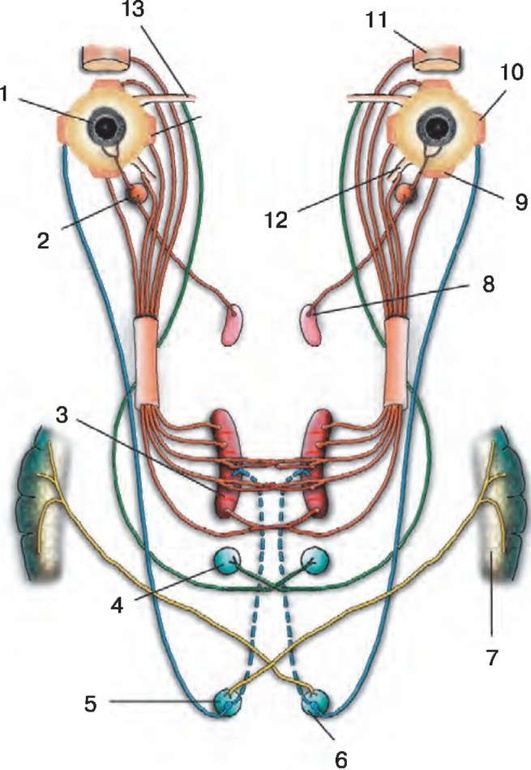

Рис. 2.1. Путь зрительных импульсов: 1 - глаз; 2 - зрительный нерв; 3 - неполный перекрест зрительных нервов (хиазма); 4 - зрительный тракт; 5 - наружное коленчатое тело; 6 - зрительная лучистость; 7 - первичная зрительная кора

Рис. 7.1. Зрительный анализатор и рефлекторная дуга зрачкового рефлекса: 1 - сетчатка глаза; 2 - зрительный нерв; 3 - хиазма; 4 - зрительный тракт; 5 - клетки наружного коленчатого тела; 6 - зрительная лучистость (пучок Грациоле); 7 - корковая проекционная зрительная зона - шпорная борозда; 8 - переднее двухолмие; 9 - ядра глазодвигательного (III) нерва; 10 - вегетативная часть глазодвигательного (III) нерва; 11 - ресничный узел